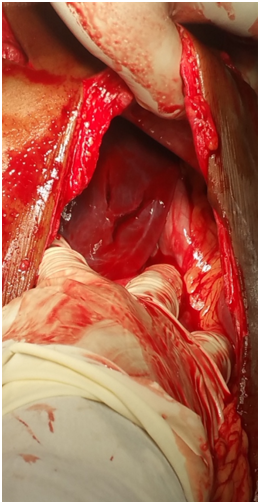

Figure 3 Stabbed heart.

Figure 4 Pericardium opened.

Figure 5 Identifying stab on heart.

The Thoracotomy and Laparotomy procedures were done. Intraoperative findings were as follows: The patient had a collapsed left lung, There was a penetrating wound in the pericardium in the right heart ventricle. The Sternum was ripped apart and the pericardial tamponade was found and Pericardial opening had to be done. The Penetrated hears was shooting the heart blood out. The stabbed heart was sutured. The abdominal stub wound revealed a tear in the stomach and a linear laceration on the left lobe of the liver. These were repaired.